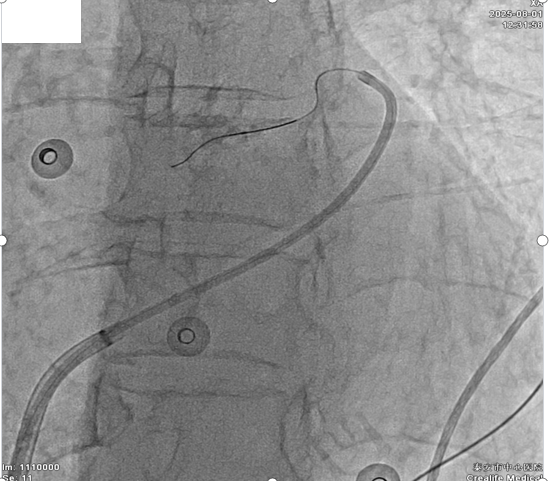

面对治疗困境,向兵团队没有退缩。凭借深厚的专业积累和创新思维,他们决定打破技术壁垒,将冠脉介入技术与心电生理标测技术深度融合,探索全新治疗路径。手术中,团队先将冠脉导丝精准送入心大静脉分支——间隔支静脉,抵达病灶附近区域。通过导丝标测技术,实现对心外膜异常兴奋点的毫米级定位,这一步如同在心脏表面开启“GPS导航”,为后续治疗精准锁定目标。

将导丝送入靶血管

在三维电解剖系统的实时监测与引导下,团队通过PTCA球囊向靶血管精准注射2ml无水乙醇。借助化学消融原理,病灶被成功灭活,室性早搏瞬间消失。为确保疗效稳定,团队继续观察1小时,患者未再出现室性早搏,手术宣告圆满成功。